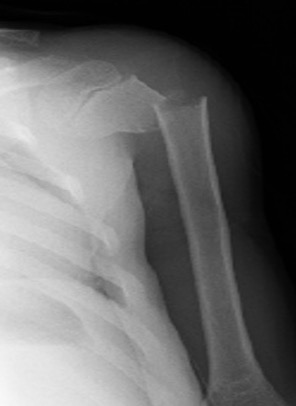

Neer-Horwitz Classification

| Type I: < 5 mm displaced | Type II - displacement < 1/3rd shaft width |

|---|---|

![]() |

| Type III - displacement 1/3 - 2/3rd shaft width | Type IV - displacement > 2/3rd shaft width |

Case: 16 year old boy

Initial injury 18 months post injury